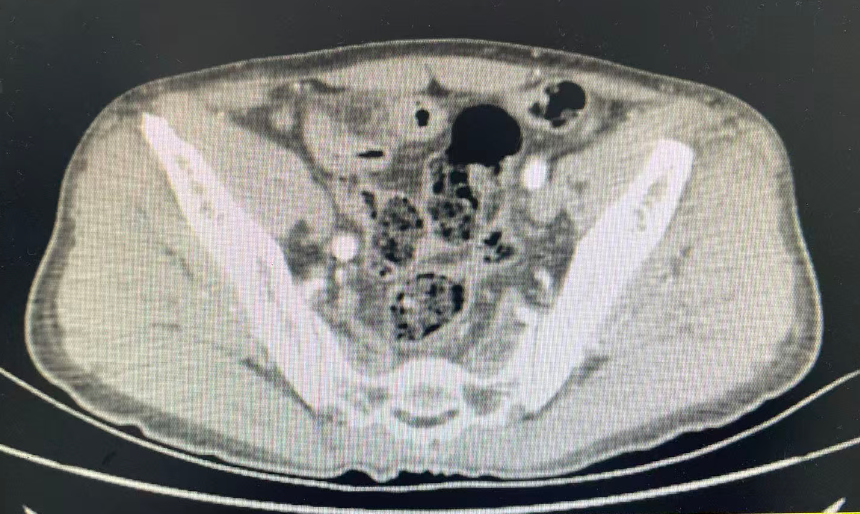

8月15日,该患者因持续加重的左下腹胀痛,来到我院消化内科就诊。接诊的张绍珠副主任医师详细询问病史并进行了仔细的查体,结合腹部影像学结果,敏锐地判断出患者存在肠穿孔可能,病情危急!

消化内科立即发出会诊邀请,外科任培土主任及杨京茹副主任迅速响应,评估病情,考虑患者乙状结肠穿孔、急性弥漫性腹膜炎,决定立即进行手术探查。医院为其开启绿色通道,启动紧急手术预案,并于当日中午由杨京茹副主任主刀,为患者施行了腹腔镜下乙状结肠切开异物取出联合乙状结肠修补术。

无影灯下,一场“缉凶”战迅速展开。在麻醉科周金萍主任团队实施的麻醉与全程监护下,手术顺利开展。术中探查发现,在患者乙状结肠中段,一根尖锐的鱼刺已完全刺透肠壁,腹盆腔有大量粪水,导致了严重的肠穿孔和腹腔感染。

杨京茹副主任随即带领团队展开精细操作:腹腔镜下顺利取出异物,见异物为一根锐利的鱼刺,长约3cm,修补穿孔肠壁,并进行了彻底的腹腔冲洗。整个手术过程一气呵成,患者生命体征平稳。